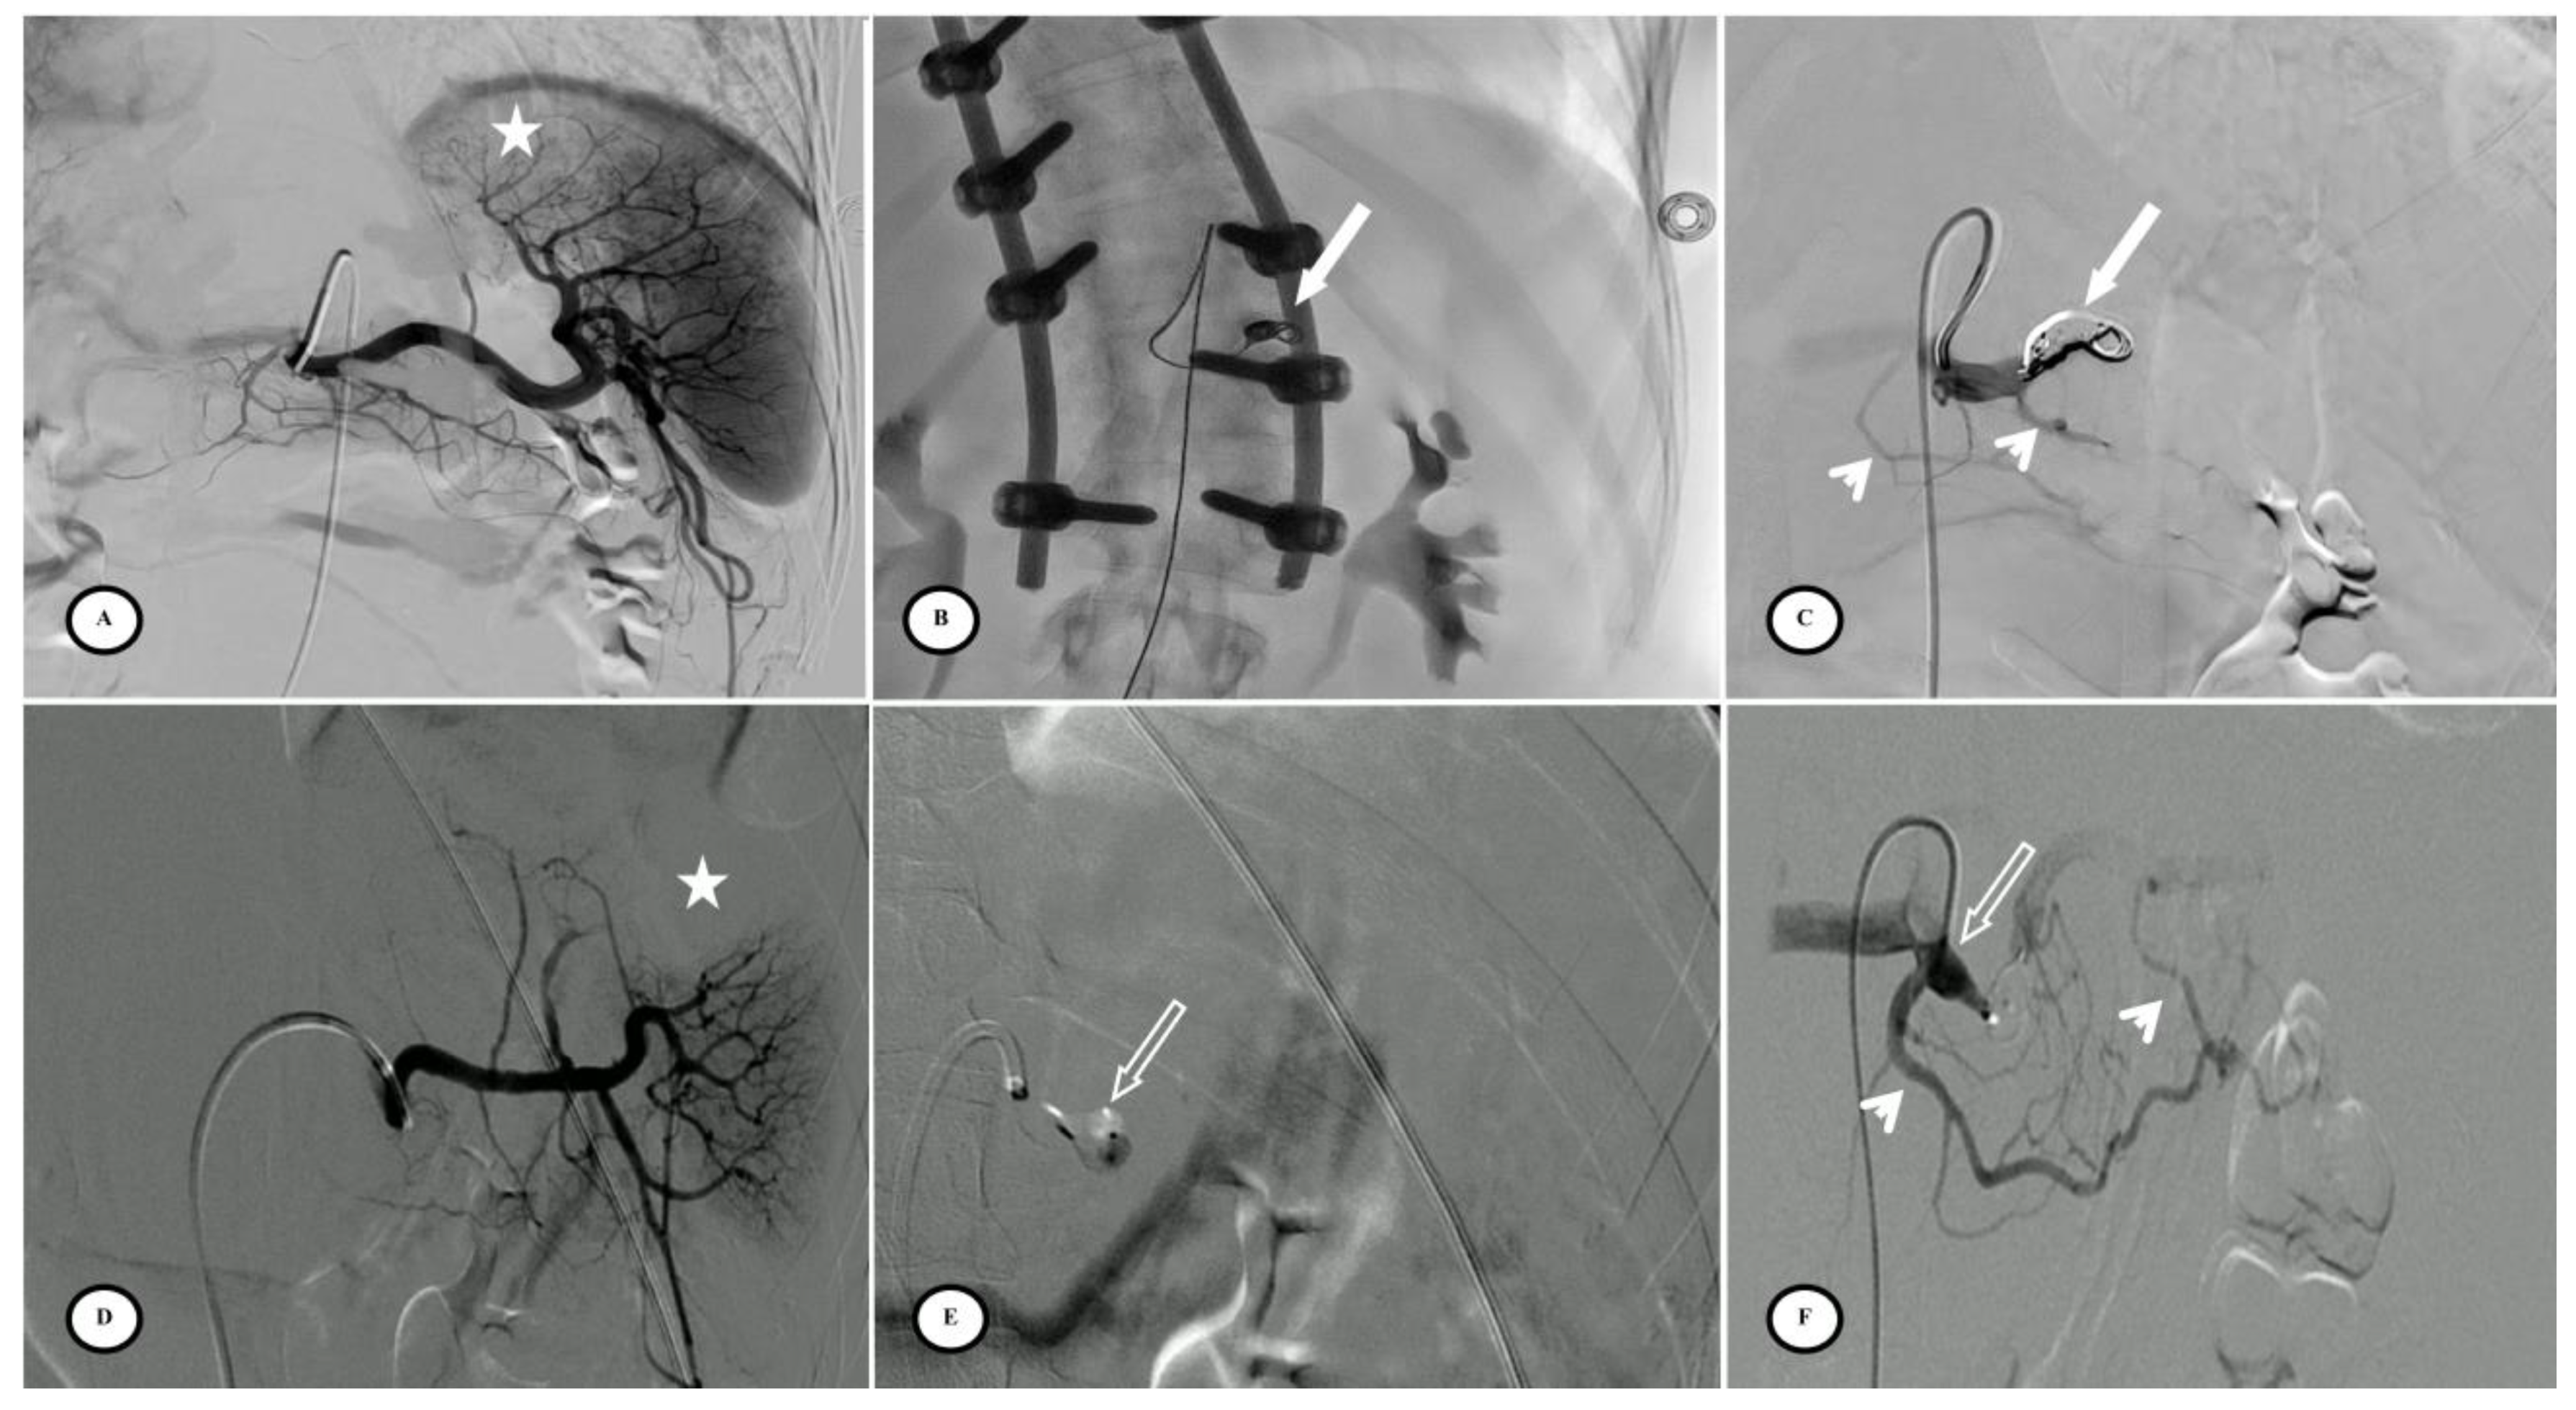

Figure 1.

Optimal site of preventive proximal splenic artery embolization. The optimal site of embolization (star) is downstream from the dorsal pancreatic artery (arrow) and upstream of the great pancreatic artery (blank arrow). Classically, at the left edge of the spine.